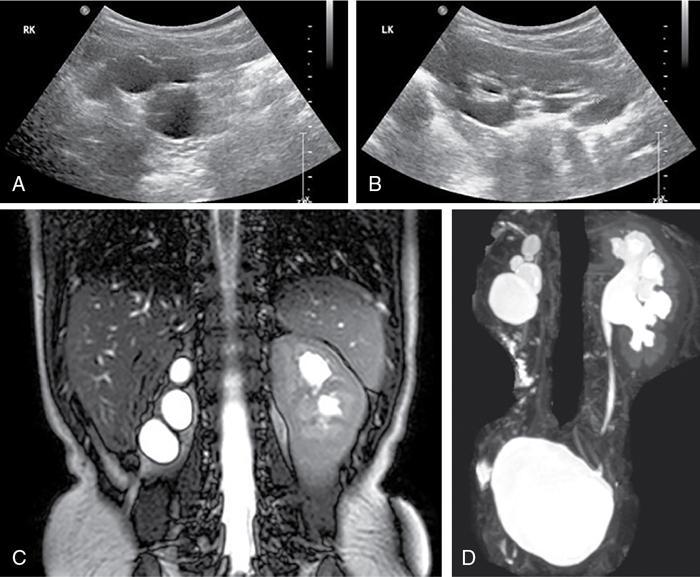

Priscilla Joshi, Vandana Jahanvi Renal anomalies encompass a spectrum which ranges from the lethal renal agenesis to incidentally detected renal anomalies secondary to aberrant embryonic migration. Imaging helps in the early diagnosis, detection of complications, surgical planning and follow-up of these patients. The kidneys develop from the pronephros, mesonephric and metanephros. These succeed each other. The intermediate mesoderm develops into the pronephros at the end of the 3rd week of gestation. This regresses a week later and is replaced by the mesonephros. The kidneys develop during the 4th week of gestation. The ureteric buds fuse with the metanephros. This occurs at the level of the first two sacral segments. In the pelvis, the kidneys are close to each other with the hila directed anteriorly. Over the next 4 weeks, the kidneys ascend into the lumbar region and move away from each other as well as rotate medially so that the hila are medially and anteriorly directed. Congenital urinary tract anomalies range from anomalies in number, anomalies in shape, cystic renal disease, collecting system anomalies and urinary bladder anomalies. These will be discussed one by one in this section. In renal hypoplasia the kidneys are small. They show a normal architecture, but the number of nephrons is reduced. The condition can be unilateral or bilateral. If unilateral the contralateral kidney shows compensatory hypertrophy. Hypoplasia if bilateral is part of genetic syndromes like renal coloboma syndrome and branchio-oto-renal syndrome. It can result in end-stage renal disease because of the reduced number of nephrons. US: A kidney which is smaller by 2 Sd as compared to the mean kidney size expected at that age. Radionuclide scan (DMSA): Rules out scarring. Less than 100 cases of this anomaly have been reported in literature. This is an extremely rare anomaly. The accessory kidneys are usually seen on the left, caudal to the left kidney. Accessory kidneys are usually smaller in size and show suboptimal function. They can be detected on ultrasound and confirmed with cross-sectional modalities like MR urography/CT urography. Function can be evaluated on postcontrast CT/MR urography or with dimercaptosuccinic acid (DMSA) and diethylene triamine penta-acetic acid (DTPA) scans. Associated urogenital or other anomalies maybe be seen. Incomplete fusion of the developing renal lobules causes a lobulated appearance of the kidneys. This has to be differentiated from renal scarring. Persistent foetal lobulations are seen as a smooth indentation of the renal outline. This is seen between the renal pyramids on ultrasound whereas the indentation in scarring overlies the renal pyramids and is not smooth and symmetrical. This can be appreciated on US, CT and MRI. This occurs due to prominent renal cortical tissue between the pyramids extending towards the parenchyma. It can mimic a renal mass on ultrasound. The interpolar region of the left kidney is a common site. It can be differentiated from a mass as it is in continuity with normal renal parenchyma and shows the same appearance as the rest of the renal parenchyma on all imaging modalities. This is a normal variation in the contour of the left kidney. The lower pole of the spleen causes an impression on the superolateral aspect of the kidney, which can mimic a renal mass. It shows the same echogenicity/density and signal intensity as the rest of the kidney. Postcontrast images on CT and MR also show enhancement akin to the rest of the kidney. Also, the calyces extend further laterally into the hump as compared to the other calyces. Infolding of the cortex at the level of the renal sinus can appear as a pseudomass, known as the renal hilar lip. As in the case of the dromedary hump the imaging characteristics of this lesion being akin to the rest of the renal tissue help reaching a diagnosis. This occurs due to embryonic fusion of renunculi. It is a normal variant which is located in the interpolar region. It occurs due to extension of sinus fat into the cortex and is seen as a triangular echogenic area on ultrasound which is in contiguity with the renal sinus fat. Differential diagnosis can include a renal angiolipoma which on ultrasound is well defined, echogenic, round, and is not in contiguity with the renal sinus fat. Simple renal cysts are rarely seen in children. An underlying genetic cystic disease or rarely a malignancy needs exclusion. The diagnosis of a simple cyst should be one of exclusion. At least one follow-up ultrasound should be done to evaluate change in size and imaging appearance as well as to rule out development of additional cysts. Further cross-sectional imaging evaluation with CT and MRI and contrast studies are not required unless atypical findings are seen initially or on follow-up. This is a severe form of renal dysplasia which may be unilateral or bilateral. Renal dysplasia occurs due to abnormal metanephric differentiation. It has an incidence of 0.3 to 1 in 1000 live births. When bilateral it is incompatible with life. The kidney is not reniform and is composed of multiple cysts of varying sizes which are noncommunicating. There is no visible functioning renal parenchyma appreciable. The collecting system and ureter are both not seen/atretic. The condition is now being detected more often on antenatal ultrasound foetal MRI (Fig. 10.7.1). The contralateral kidney, if normal, shows compensatory hypertrophy. Sequelae such as hypertension, proteinuria and renal impairment are uncommon as is contralateral VUR, PUJO. There is no increased incidence of malignancy reported. US: Multiple cysts of varying sizes which are noncommunicating are seen. The kidney may be enlarged and even palpable in neonates. Subsequently, the kidney may involute. The contralateral kidney shows compensatory hypertrophy. CT/MR: It shows similar findings. The kidney is nonfunctioning on postcontrast CT/MR or a DMSA scan. The ureter may be atretic. ARPKD is a paediatric cystic renal disease with an incidence of 1 in 10,000 to 40,000 live births. There is no gender predilection. This condition results from mutations in the PKHD1 gene on chromosome 6p12 that encodes for the protein fibrocystin. The earlier the diagnosis is made the condition will be more severe. This condition manifests itself at the age of 30–40 years. It is one of the most common genetic disorders caused by a single gene mutation with an incidence of 1 in every 1000 individuals The kidneys are enlarged (Fig. 10.7.4) and contain multiple cysts of varying sizes. There is deterioration of renal function leading to renal insufficiency. In the neonate, the cysts may be very small and discrete. In children without a genetic diagnosis or a clear family history where the condition is detected, a follow-up USG should be performed within 12 months of the initial detection.

ADPKD: Autosomal dominant polycystic kidney disease